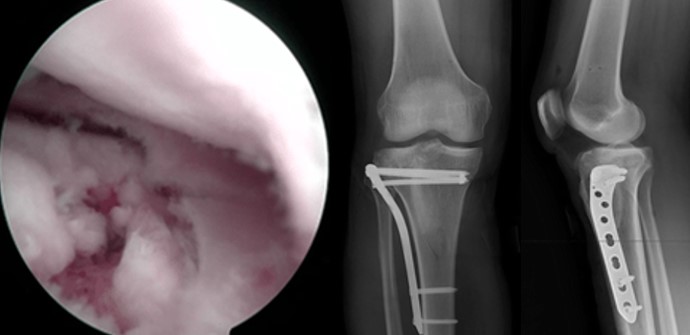

Артроскопічно - асистовані операції дозволяють мінімізувати травматичність втручання, здійснити точну репозицію суглобової поверхні під візуальним контролем, діагностувати та лікувати супутні внутрішньосуглобові пошкодження м’яких тканин: менісків та зв'язок.

Відкрита репозиція та внутрішня фіксація залишається золотим стандартом лікування. Використовують різні хірургічні доступи залежно від локалізації перелому. Фіксацію здійснюють кутовими пластинами з кутовою стабільністю, гвинтами, спонгіозними гвинтами з шайбами. При наявності кісткового дефекту виконують кісткову пластику.

Показання до операції: зміщення суглобової поверхні більше 2-3 мм, нестабільність колінного суглоба, відкриті переломи, пошкодження судинно-нервових структур, пошкодження внутрішньосуглобових структур: меніски та зв’язки.

- Анатомічна репозиція суглобових поверхонь (міжуламкова компресія, опорна функція)

- Ревізія/дебридмент внутрішньосуглобових мякотканинних структур (меніски, зв’язки)

- Відновлення механічної осі

- Стабільна фіксація